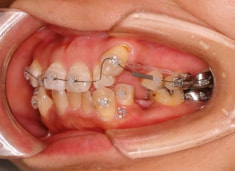

治療開始時

治療開始から約1年2ヶ月後